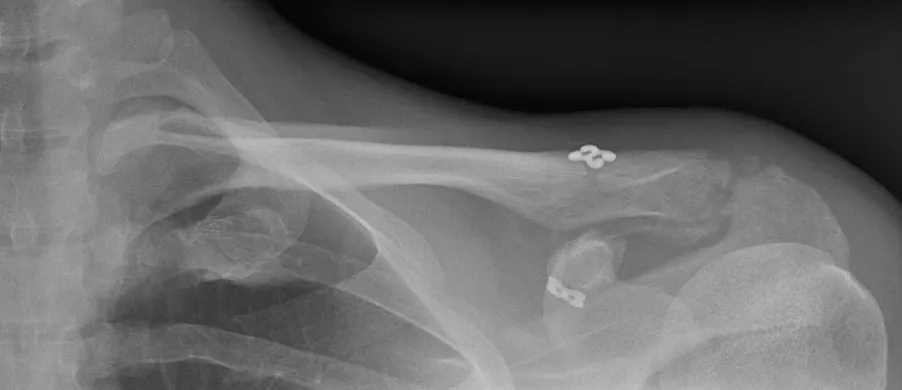

Il existe une déformation de la face supérieure de l'épaule avec un aspect saillant de l'extremité latérale de la clavicule sous la peau. L'importance de la déformation est variable en fonction de la gravité des lésions.

Dans un premier temps des radiographies permettent d'avoir une orientation diagnostique en corrélation avec l'examen clinique du chirurgien. Des clichés comparatifs (des deux épaules) permettent d'affiner le diagnostic. Un scanner avec des reconstructions tridimensionnelles peut être utile dans certains cas.